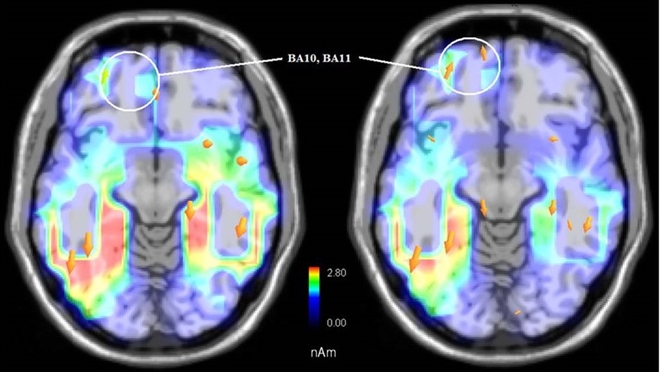

EEG và fMRI ghi nhận tín hiệu “dự đoán”

Các thí nghiệm gần đây sử dụng EEG và fMRI để quan sát não khi người tham gia được trình chiếu các sự kiện ngẫu nhiên. Kết quả cho thấy một số sóng não phản ứng trước khi sự kiện xảy ra, mở ra giả thuyết về cơ chế dự đoán của não bộ.